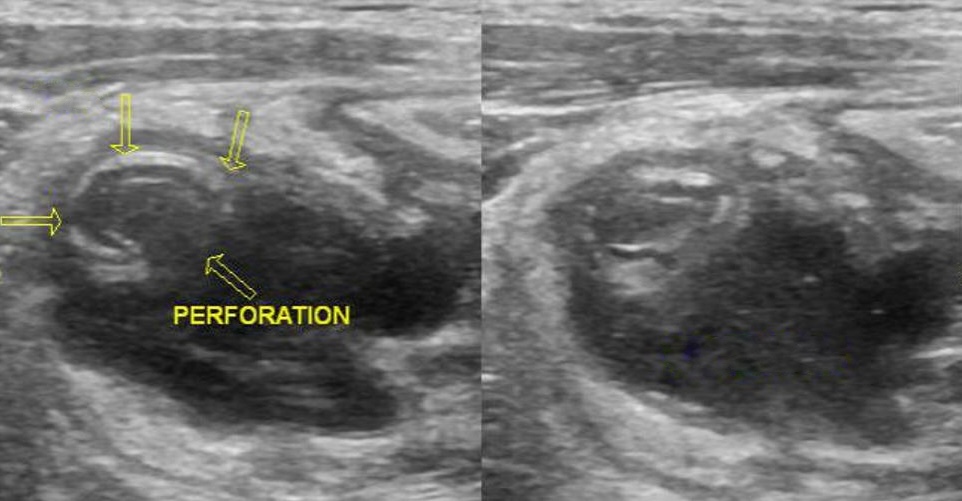

arguments pour une invagination iléo-colique

- diamètre > 2 cm et longueur > 3 cm

- ganglion ou appendice dans le boudin

- jonction iléo-colique non visualisée

lavement eau sous scopie = 1 m de pression

= 90% réussite mais 2% perfo et 20% récidive